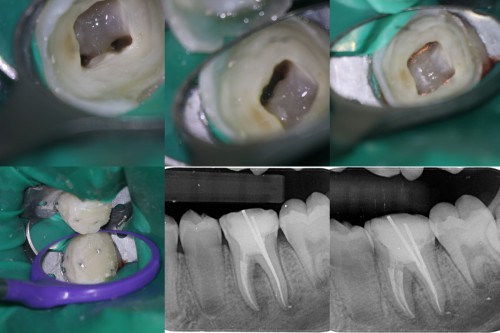

Nice cases. For the maxillary molar, did you use a saddle matrix on the second stage amalgam?

Yes, I used a saddle matrix.

I bought some saddle matrices but have yet to use them. Do you find you get a tight contact?

Yes Dr

Dr. Miglani,

You demonstrate some very accomplished skills…..these are not easy restorations to do well. The enod also looks very carefully done. Keep it up!

Great execution Revathi both on the restorative and the endodontic aspects ,especially in hard to isolate areas.